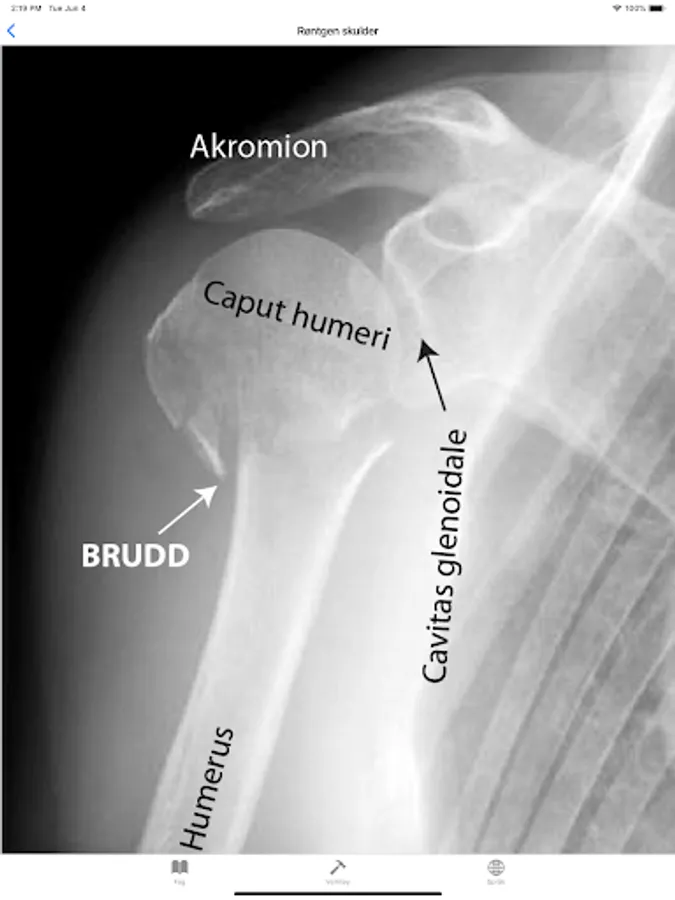

Fracture proximal humerus